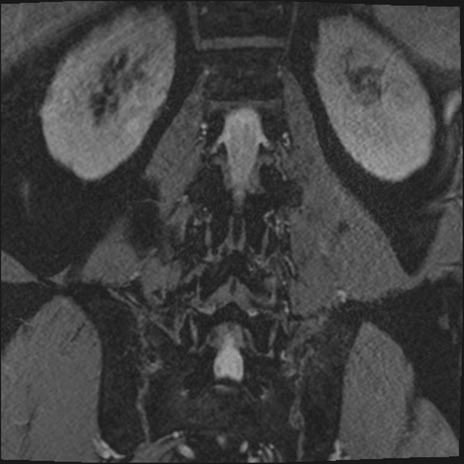

【整形】TIPS症例2 腰椎MRI 3D(冠状断像)

【症例】70歳代男性

【主訴】左下肢痛

【現病歴】2週間前くらいから腰痛、左下肢痛あり。左臀部から大腿、下腿外側のしびれが常時ある。歩行とともに同部位の痛みあり。

【身体所見】Lasegue70-/60+、Bragard-/±、PTR ±/±、ATR -/-、IP 5/5、TA 5/4、TS 5/5、EHL 右第1足趾なし/3、FHL 5/5、hypersthesia(-)、足背動脈触知良好

異常所見と診断は?